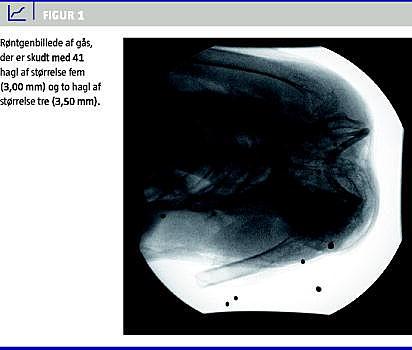

Go for the evidence som Gil Grissom i Crime Scene Investigation (CSI) siger. Gennemlysning af gåsen viste, at den var ramt af adskillige hagl. I Skotland anvendes blyhagl, og disse ses deformerede med god energiafsætning (Figur 1 ). J anvendte haglstørrelse fem (3,00 mm) og G anvendte haglstørrelse tre (3,50 mm). Det ses, at gåsen er ramt af adskillige hagl af størrelse nr. 5 og mindst et hagl af størrelse nr. 3, det sidste med gennemskydning af thorax. Konklusionen er således, at begge jægere ramte gåsen dødeligt, men at J's skud som følge af den voldsomme energiafsætning var det umiddelbart dræbende. J fik sin julegås, og det skotske gods forærede G en anden gås som trøst!